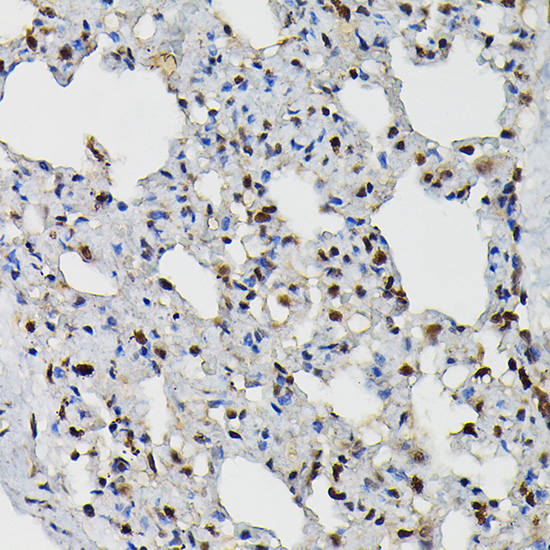

Immunohistochemistry of paraffin-embedded rat lung using PRPF4 Rabbit pAb.